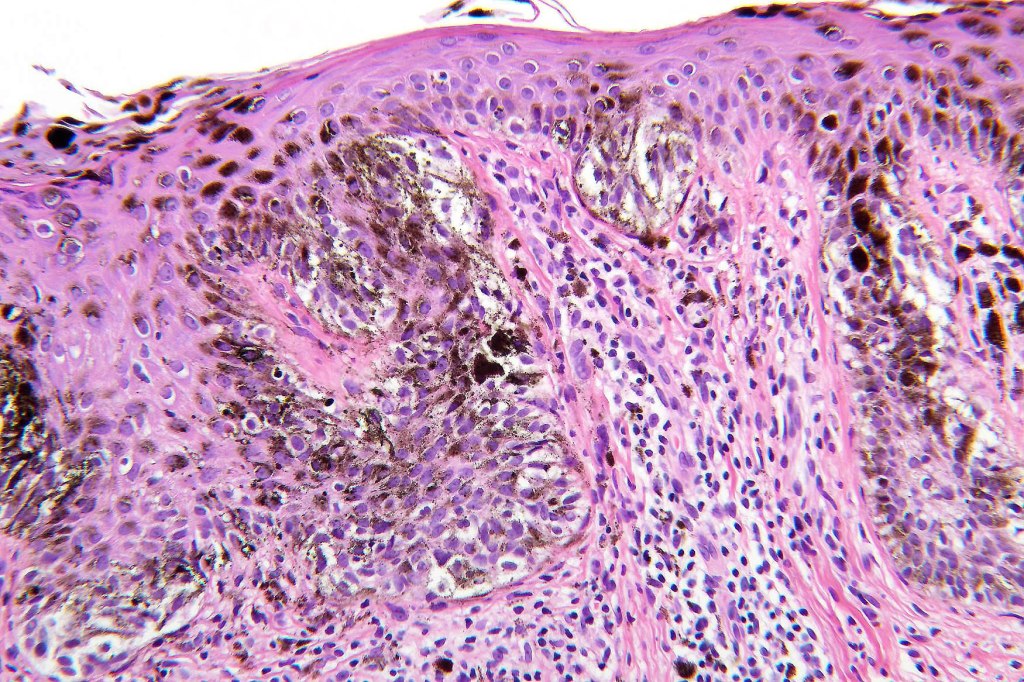

Histological features

•May affect the tumor in part or whole

•Enlarged cells with copious eosinophilic, foamy or clear cytoplasm (some authors include melanoma with clear cell change in the same category)

•Variable pigmentation

•Nuclei vesicular or hyperchromatic

•Pleomorphism is not generally marked and indeed can be very subtle

•Variable mitotic activity

•Thought to be a result of abnormal or degenerative melanosome change